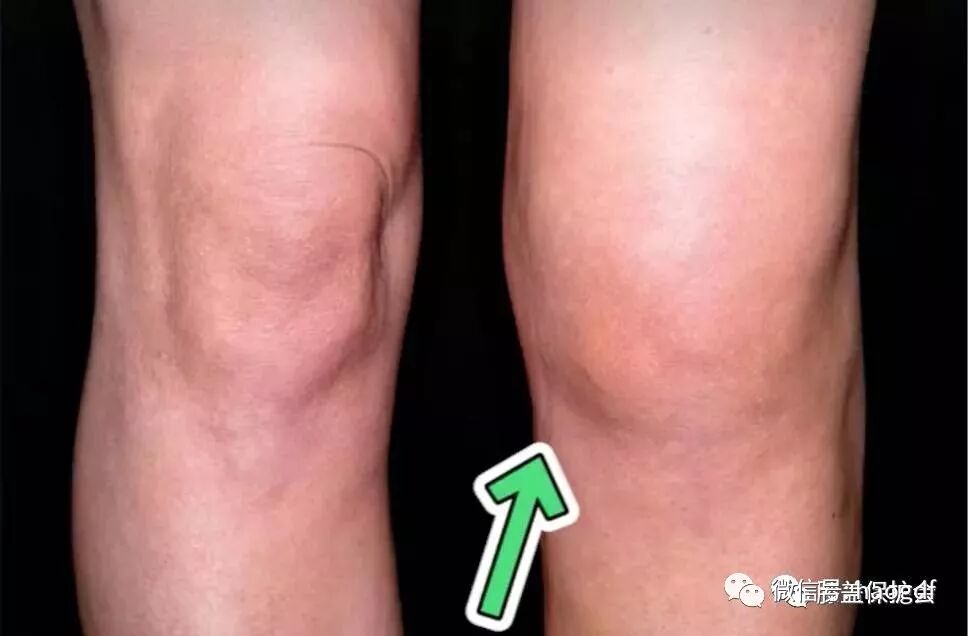

另外这个膝盖变形的征兆还会附加一条,内侧变得比较肿胀。甚至有些人会一边膝盖有退化,另一边没有退化,你会发现有退化的那个膝盖是有很明显的肿胀的。

这个问题通常是它在变形的过程中,导致周围的韧带还有肌腱发炎比较严重,所以它也跟着发炎到肿胀。

关于膝窝囊肿,它有个学名,叫贝克氏囊肿。

很多人发现膝盖窝后面肿了一个大颗后,会惊恐是不是长了肿瘤,然后紧张的去看肿瘤科。这个贝克氏囊肿其实是因为你的膝盖退化的太严重了,导致关节囊产生了一点点破裂,里面的关节液往后侧流入,在后面积成了一个小球。

如果你现在已经有了这样的问题,膝盖后面肿得跟馒头一样大了,你可以去找医生,把里面得组织液抽取出来。